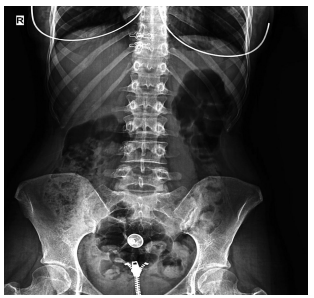

Dose reduction was used in patients with moderate and severe back pain, constituting 37.2% of the patients describing the complaint. The vast majority of these patients responded to dose reduction, while eight (10.2%) patients needed to use non-steroidal anti-inflammatory drugs for pain relief. Sacroiliitis was present in four (4%) patients, including three females and one male. There was no statistically significant difference between the sexes for sacroiliitis development (p=0.25). Bilateral sacroiliitis was detected in one patient (Figure 1). Sacroiliitis regressed 1.5 to 2.5 months after isotretinoin treatment cessation in all patients. The patients diagnosed with sacroiliitis were followed for six months. Three (3%) patients described myalgia, which was of mild severity and did not require additional treatment. Among these patients, two female patients also described low back pain. Creatine kinase (CK) elevation was observed in 18 (18.1%) patients, including 13 males and two females, one to three months after the beginning of treatment (p=0.1). The elevated CK values ranged between 233 and 940 IU and returned to normal levels after dose reduction. One (1%) female patients who was on low-dose isotretinoin treatment (0.5 mg/kg) was diagnosed with enthesitis at three months of treatment (Figure 2).

Enthesopathy is a reported side effect of isotretinoin and usually develops after long-term isotretinoin use.[37,38] However, cases associated with short-term isotretinoin treatment have also been reported in the literature. Tendinitis of the Achilles tendon is a known side effect of isotretinoin and has been reported in 9.5% of patients.4 A close relationship between Achilles tendinitis and isotretinoin dose has also been described.[39,40] In our study, the patient who developed tendinitis was on low-dose isotretinoin treatment. Dose reduction and interruption can be considered in patients developing tendinitis.[39] The symptoms of the patient in the current study regressed with the cessation of treatment.